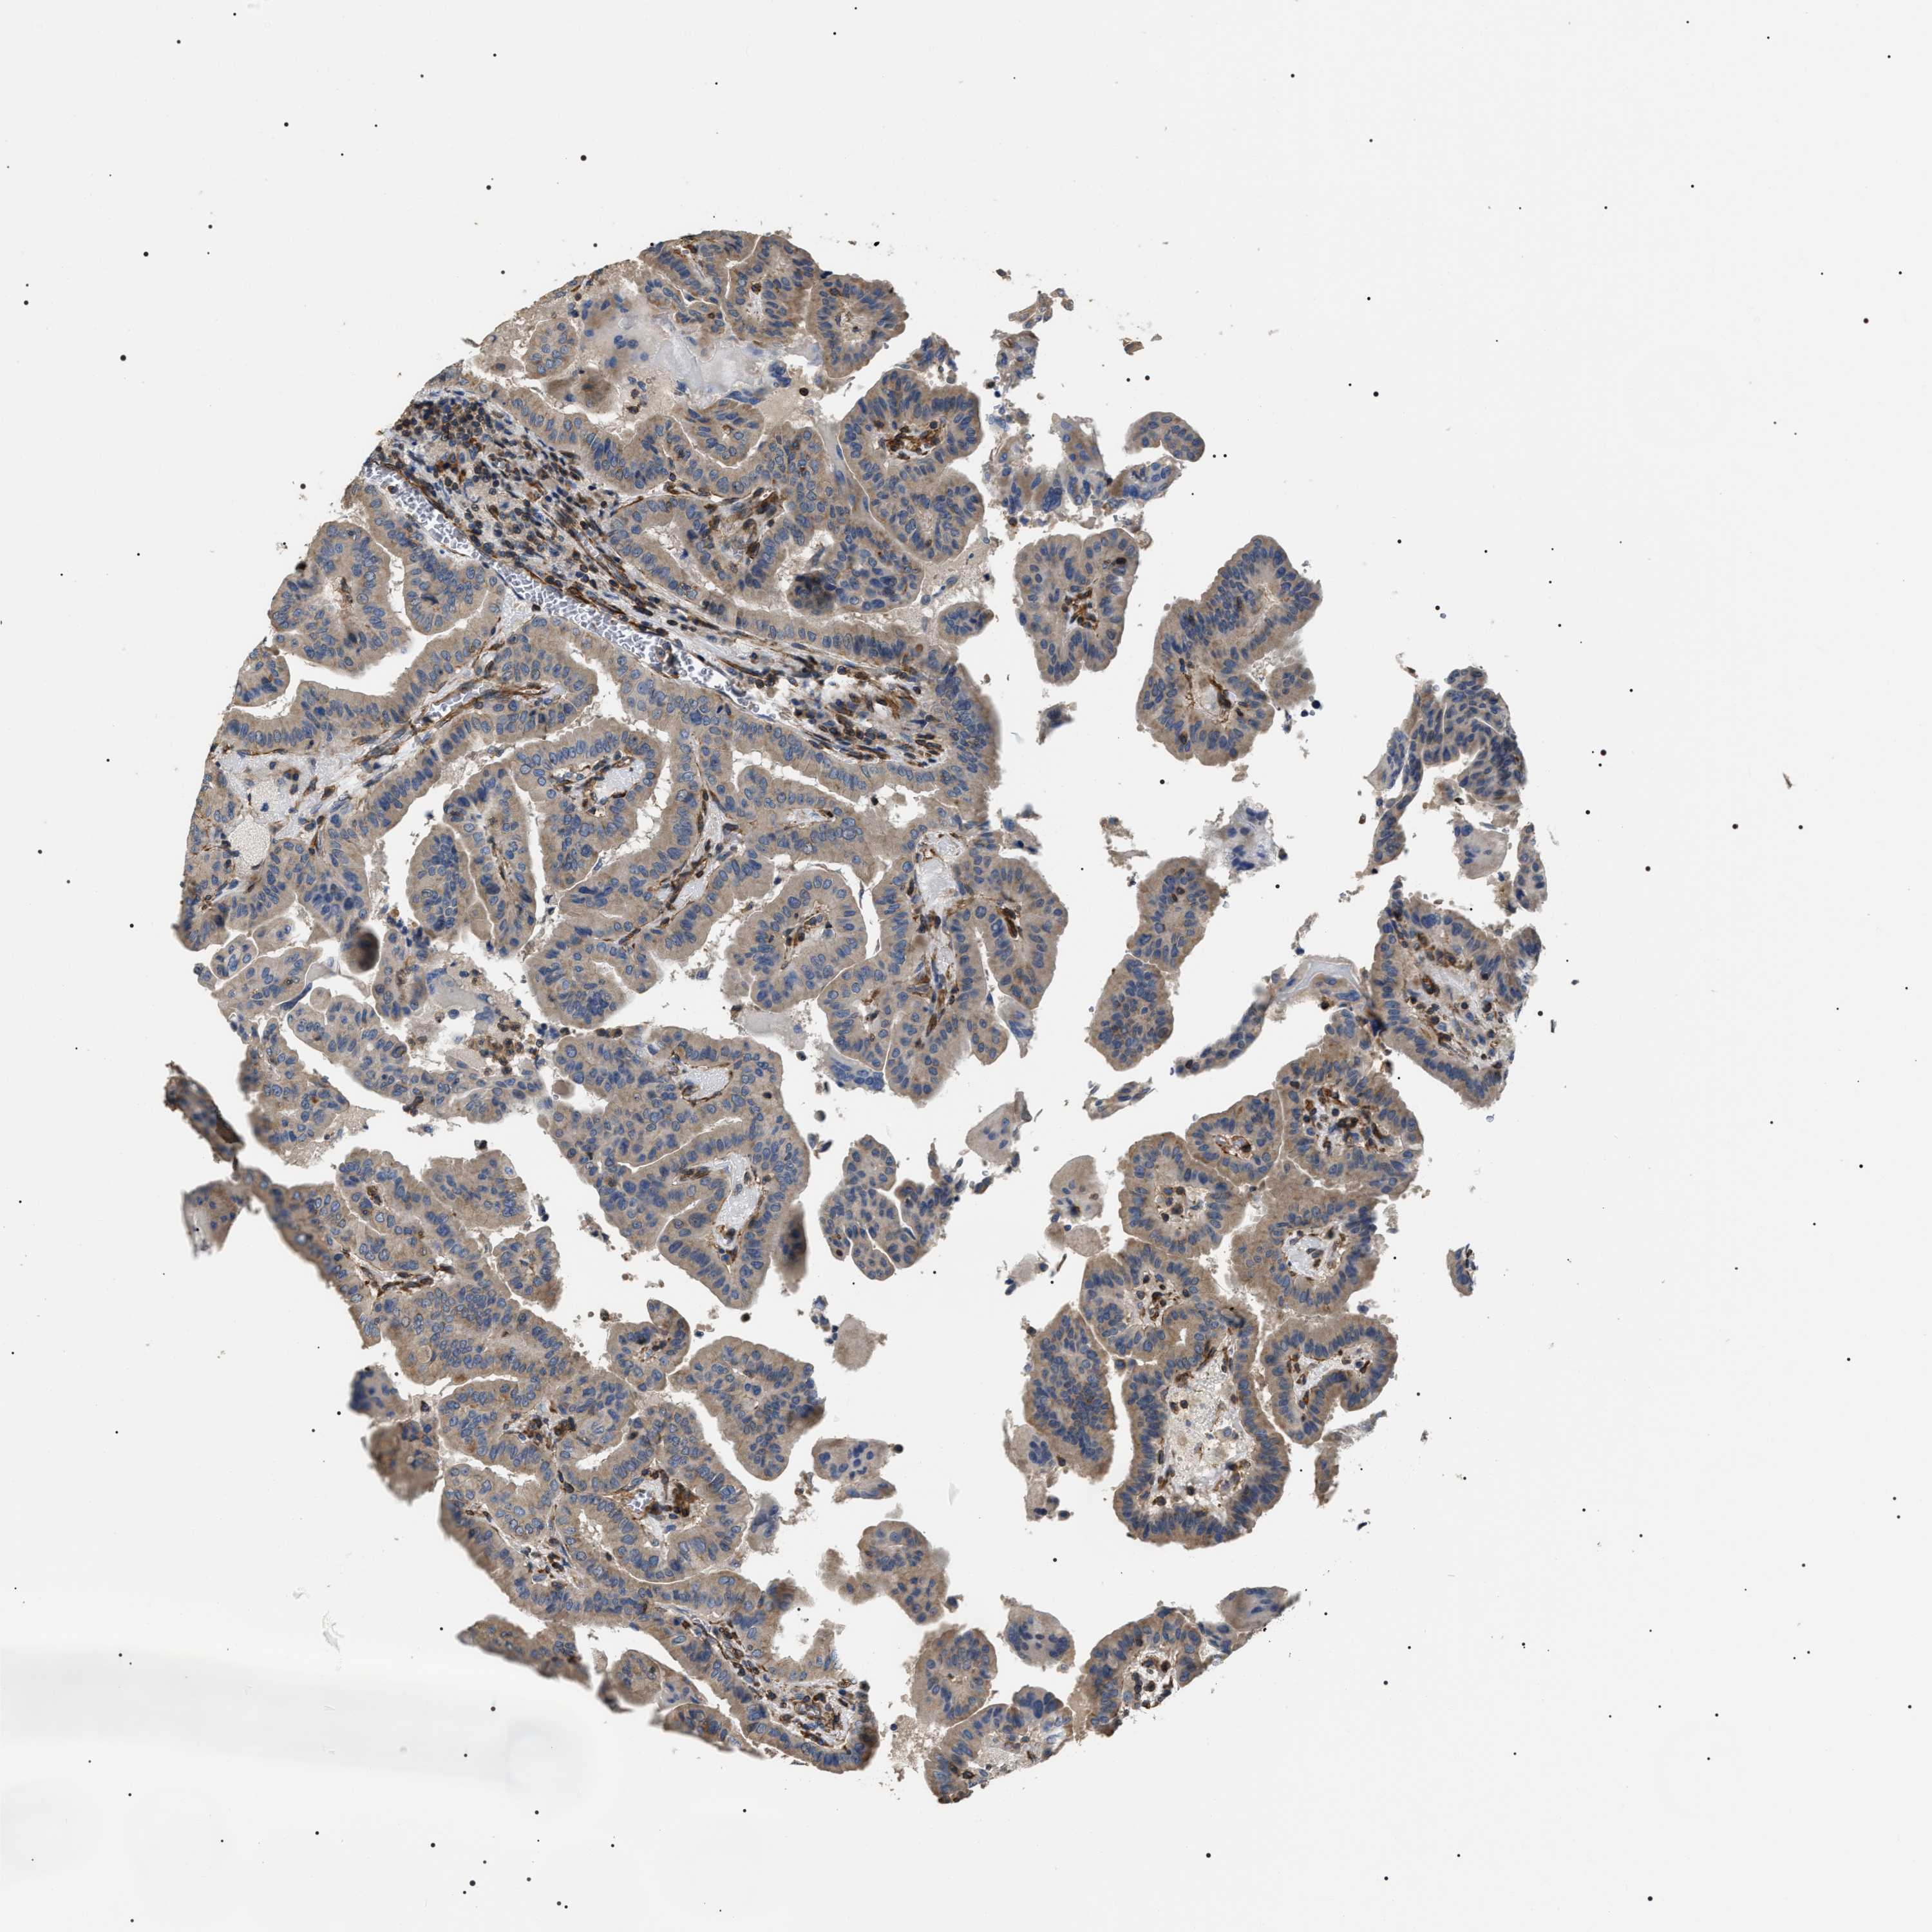

THYROID CANCER - Protein expressioni

A mouse-over function shows sample information and annotation data. Click on an image to view it in a full screen mode. Samples can be filtered based on level of antibody staining by selecting one or several of the following categories: high, medium, low and not detected. The assay and annotation is described here.

Note that samples used for immunohistochemistry by the Human Protein Atlas do not correspond to samples in the TCGA dataset.

Antibody stainingi

Antibody staining in the annotated cell types in the current human tissue is reported as not detected, low, medium, or high, based on conventional immunohistochemistry profiling in selected tissues. This score is based on the combination of the staining intensity and fraction of stained cells.

Each image is clickable and will lead to virtual microscopy that enables deeper exploration of all samples and also displays staining intensity scores, fraction scores and subcellular localization as well as patient and tissue information for each sample.

Antibody HPA020386

Staining

High

Medium

Low

Not detected

Intensity

Strong

Moderate

Weak

Negative

Quantity

>75%

75%-25%

<25%

None

Location

Nuclear

Cytoplasmic/membranous

Cytoplasmic/membranous,nuclear

Papillary adenocarcinoma, NOS

Follicular adenoma carcinoma, NOS